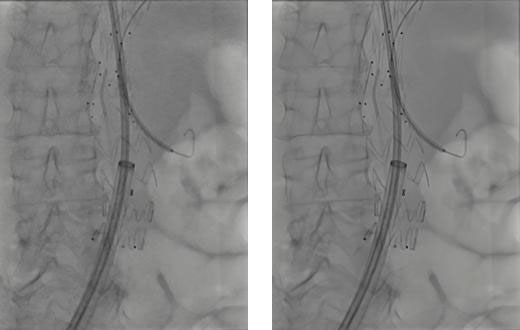

さらに、AIを活用した高度なアルゴリズムにより、2D透視・撮影モードおよびさまざまな部位において、信号強度を維持したまま量子ノイズや電子ノイズをリアルタイムに低減。微細な血管やカテーテル、ガイドワイヤーなどの治療デバイスを明瞭に確認でき、良好な視認性を確保する。

AIにより鮮明な画像を得られることで、操作性や診療の質の向上だけでなく、診断参考レベルを大きく下回る線量での検査・治療が可能となり、患者および医療従事者の被ばく低減に貢献するとしている。